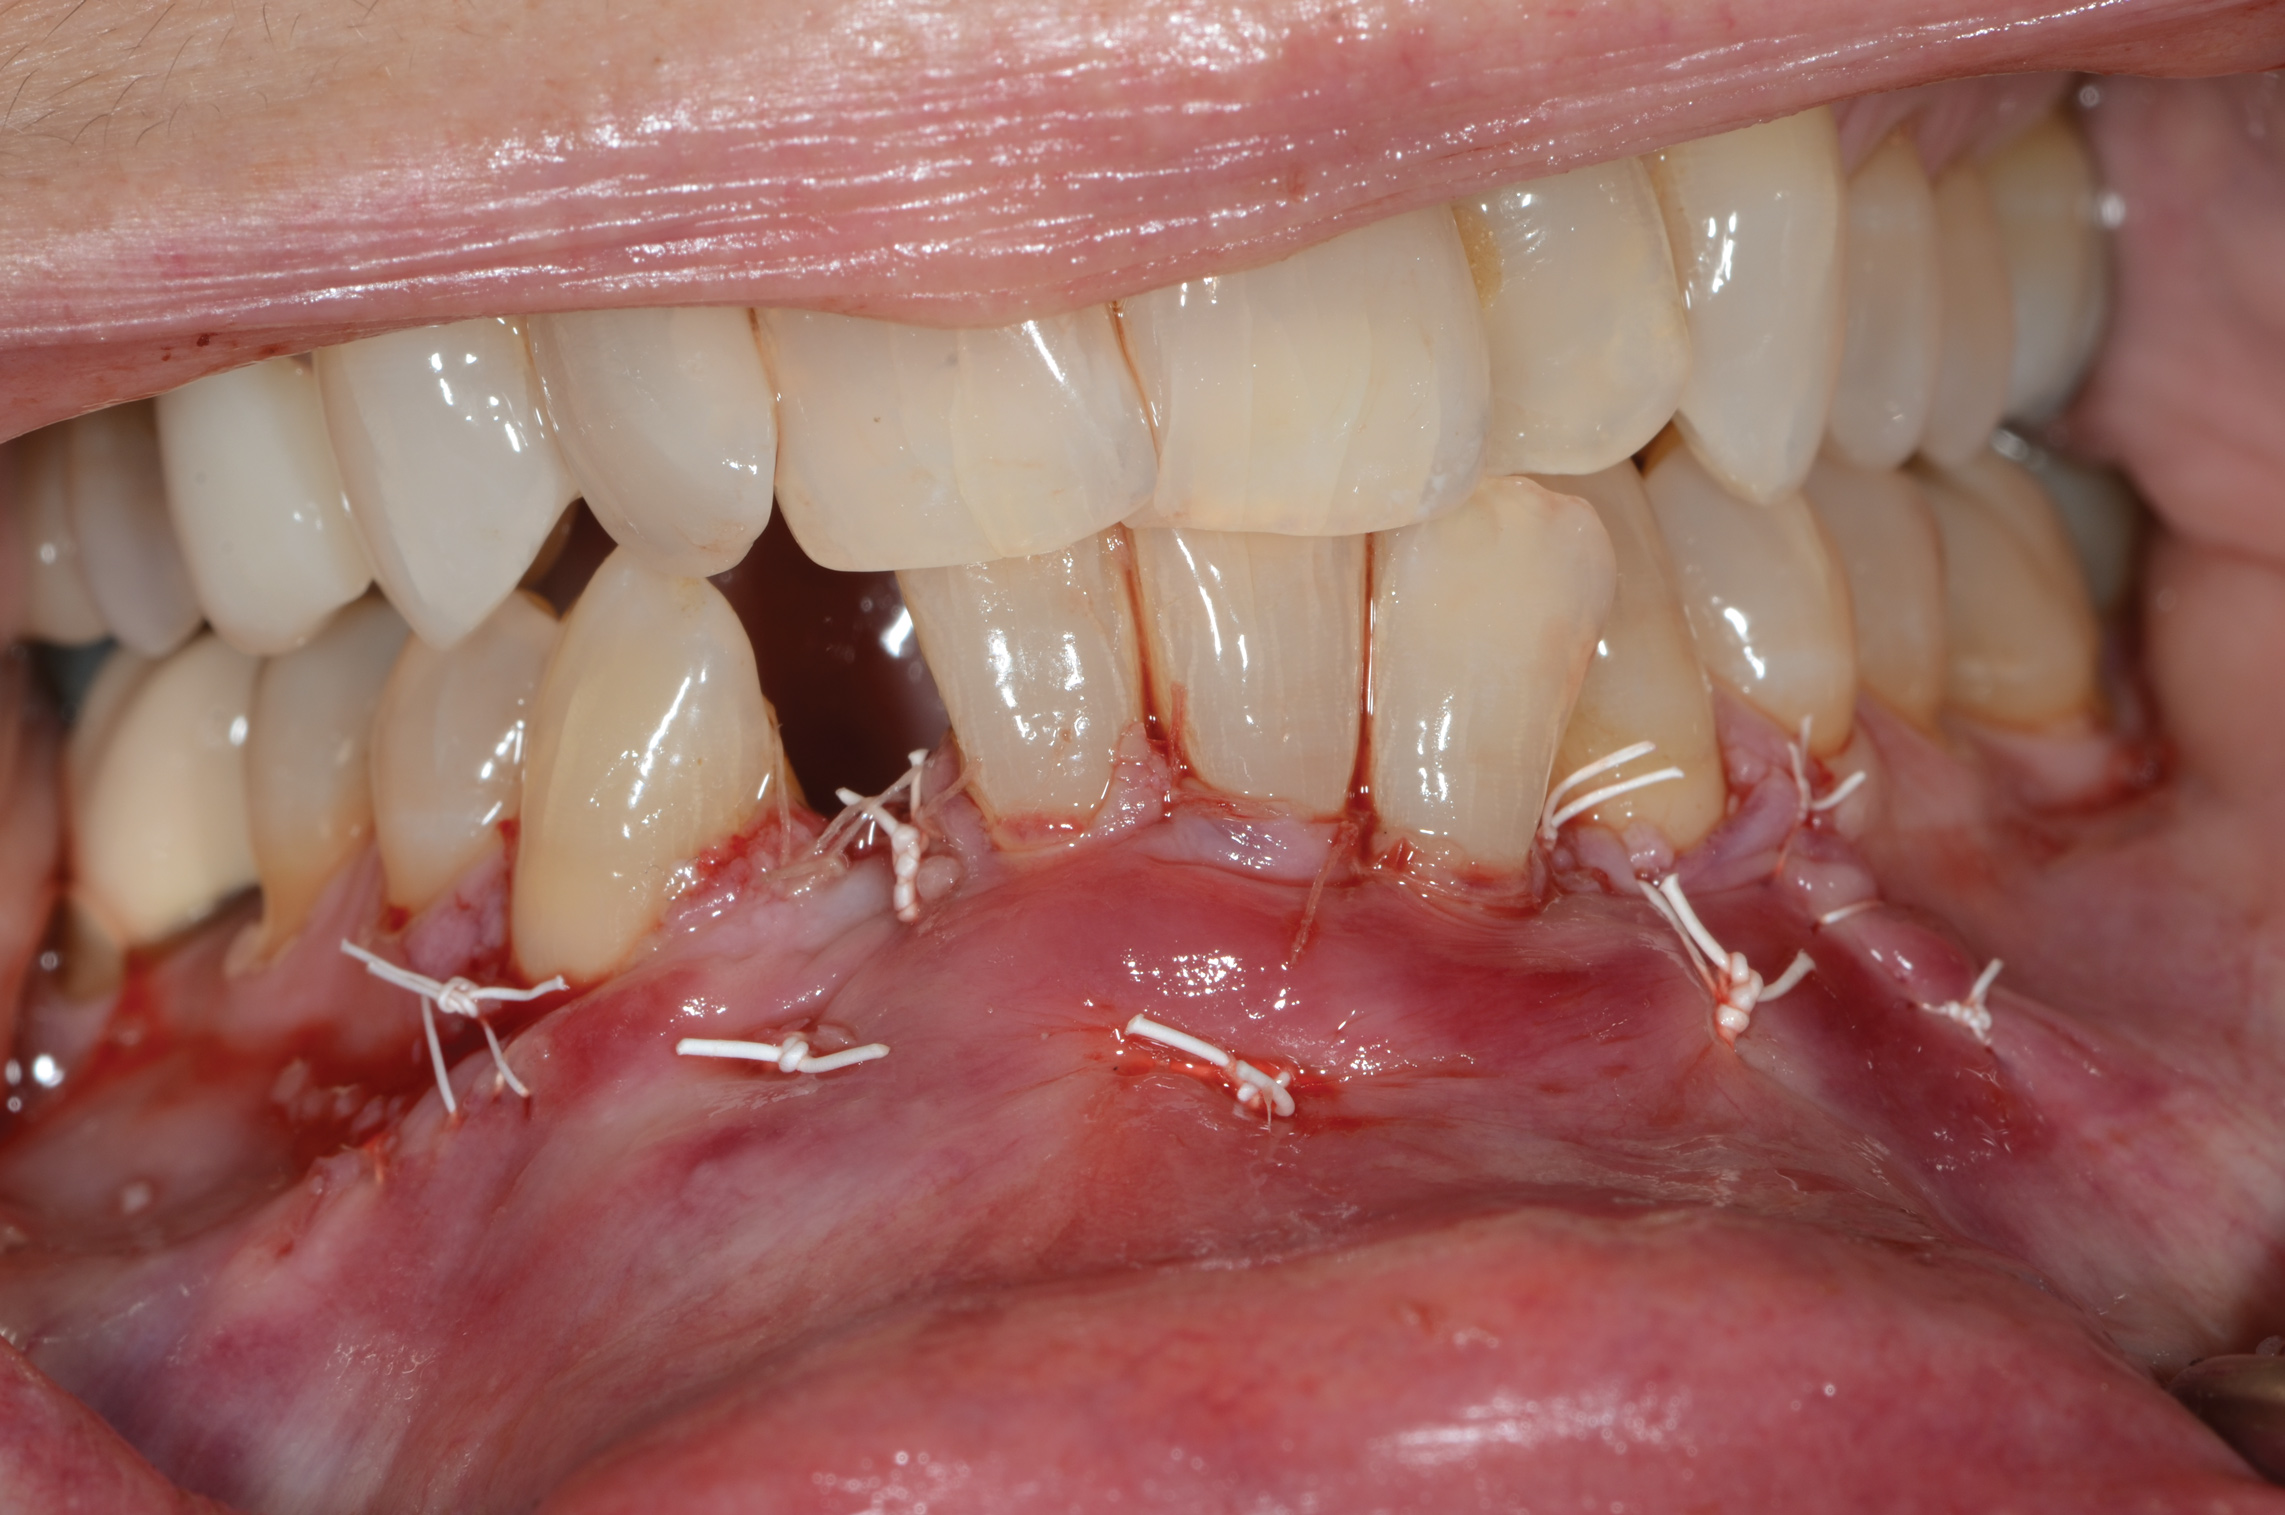

Fig 11. Suturing after SFOT procedure; note the shallow vestibule and flap tension at closure.

Figure 11